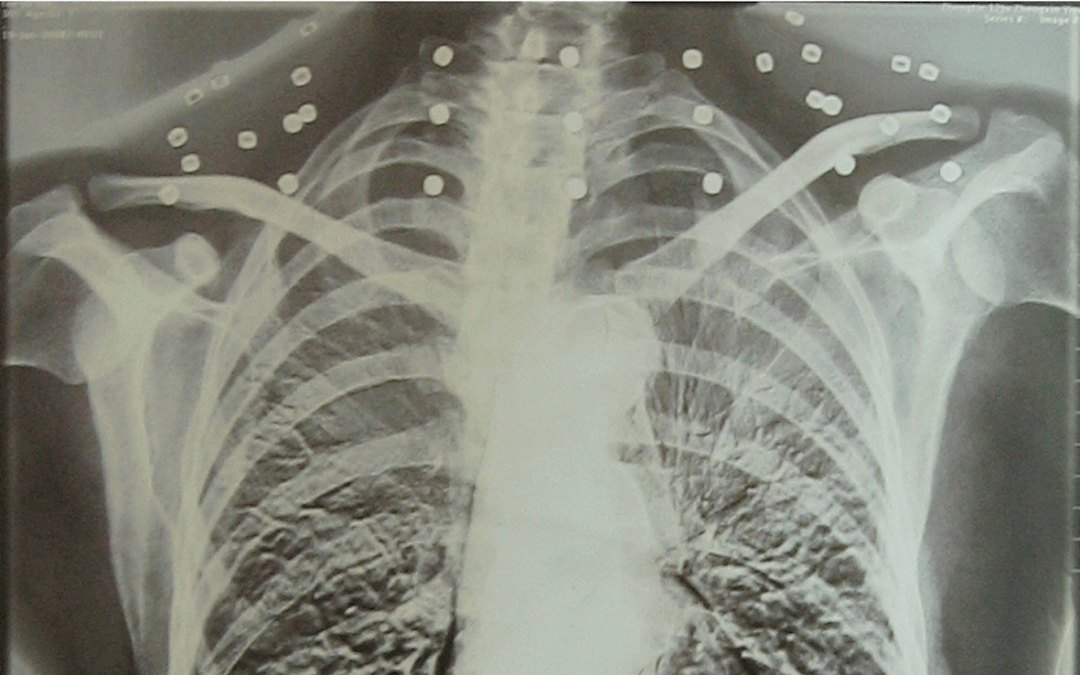

這張照片

是今年82歲的吳以先老人

拍攝的一張CT照

但實際上是

吳以先的頸部和腹部

共分布著33枚彈片

宏鑫機械設備有限公司 他體內(nèi)的彈片都沒有取出

每到天氣變化時

身體留有彈片的位置就有痛感

與吳以先身上那33枚彈片